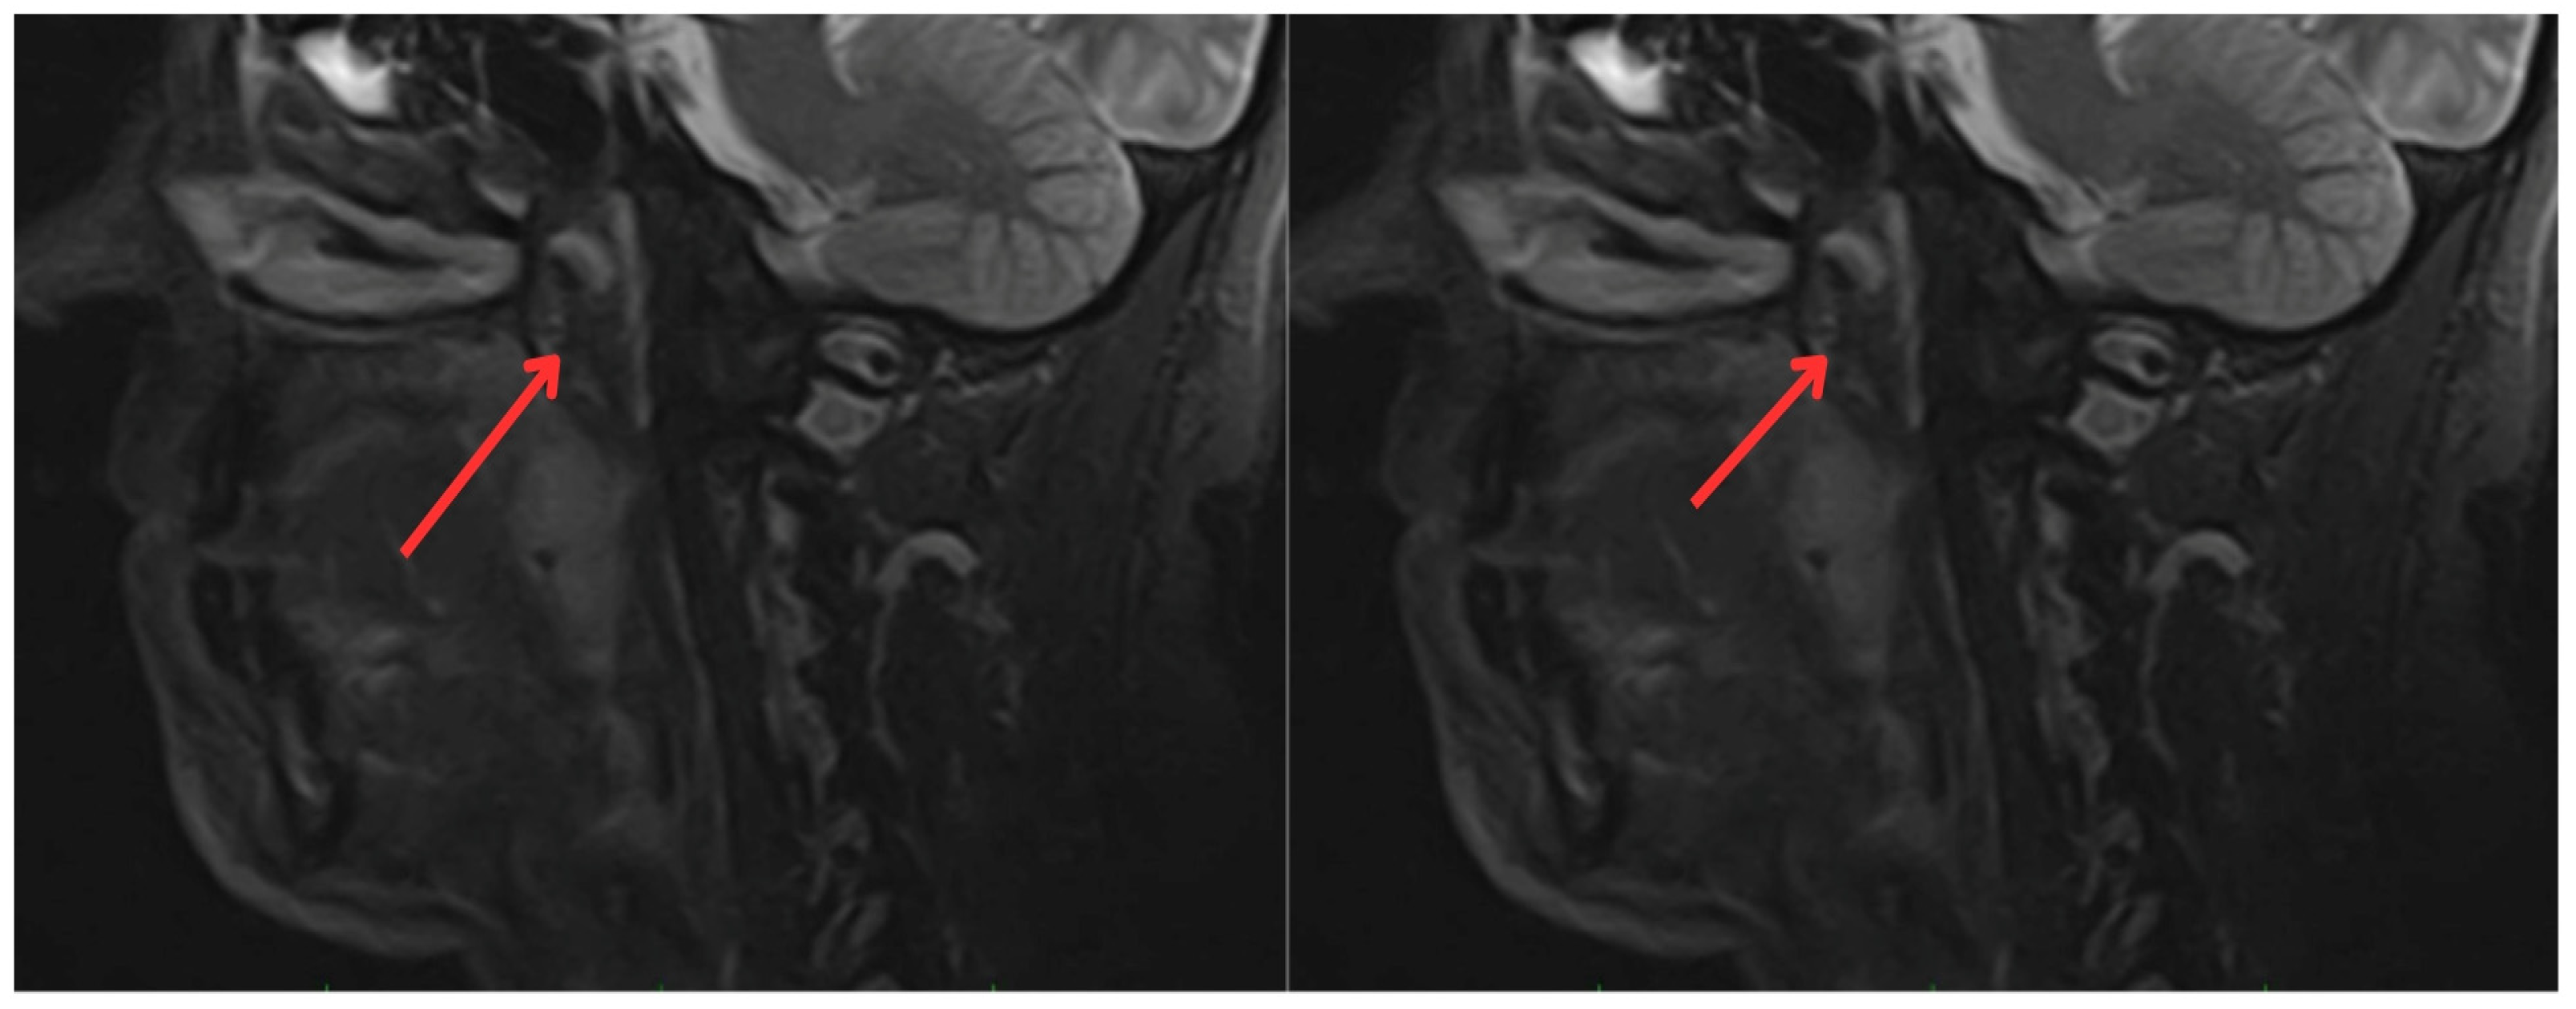

2. Case Report